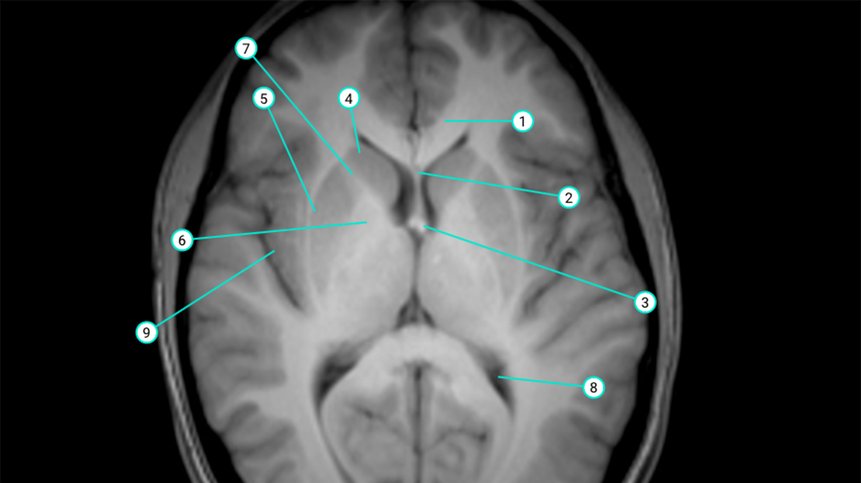

Anatomy tutorial

This online anatomy tutorial supports medical students and students from related disciplines in preparing for their exams. Besides textbook drawings, the course shows photos of anatomical preparations as well as radiological images. The tutorial was developed in collaboration with the Anatomical Institute of the University Basel and is freely accessible.